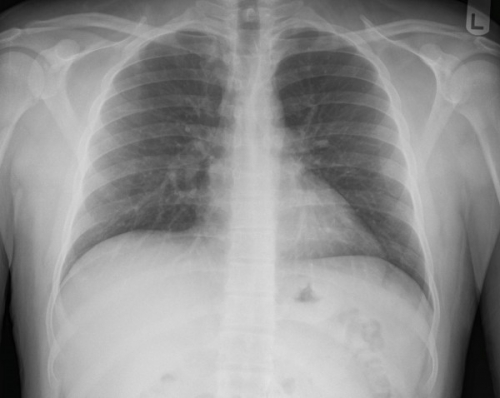

Tool to train medical student's eyes as to what a normal chest x-ray looks like, with over 500 consecutive normal images.